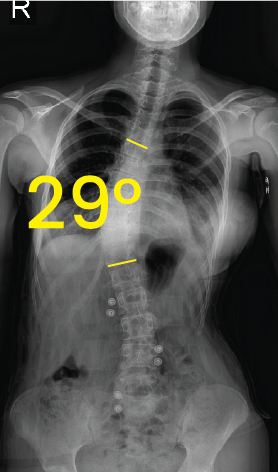

Göğüs röntgeninde omurgada 38 derece skolyoz açısını gösteren sarı çizgiler ve 38° rakamı.Göğüs ve lomber omurgada 29 derece skolyoz eğrisi gösteren röntgen görüntüsü.